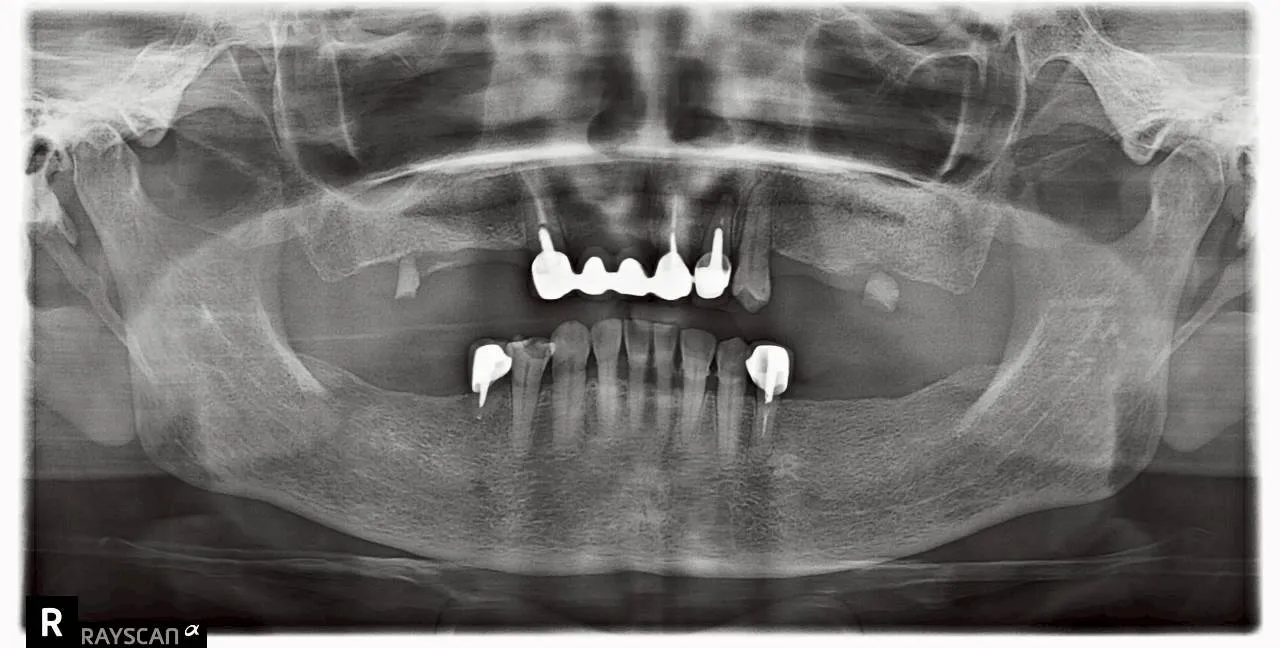

全口植牙重生紀實:找回咀疊的日常幸福

案例背景:那些被遺忘的味覺記憶

「醫師,我很久不知道大口吃肉的感覺了。」患者初診時的這句話,道盡了長年缺牙的無奈。

缺牙引發的連鎖反應

• 咬合功能崩塌: 僅靠前牙支撐,進食成了沈重負擔。

• 社交自信流失: 習慣性遮嘴,甚至推辭與家人的美食約會。

診療計畫:為生活品質開立的專業處方

謝昂儒醫師深知,植牙不只是補牙,更是重建生活。我們針對患者全口咬合不穩的現況,制訂了精準的植牙藍圖。

穩固基石的建立

• 力學回歸: 植體如基石般穩固,為全口提供對咬支撐。